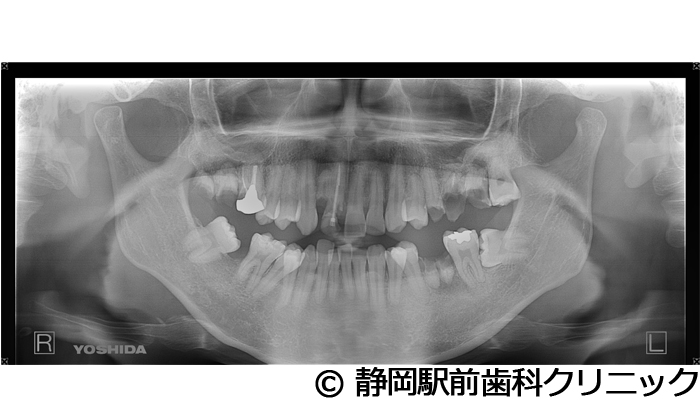

【症例5】全顎的インプラントとセラミックによる審美補綴

- 治療前

- 治療後

- 治療名

- 全顎的インプラントとセラミックによる審美補綴

- 費用

- 1,800,000円(税込)

- 期間

- 1年6ヵ月

治療内容

患者様の症状

全体的に歯がないため、噛めない。インプラント治療希望。

治療方法

全体的に残根は抜歯を行い、術前にCTを撮影し緻密に治療計画を立てた。インプラント埋入はブロックごとに行い、噛み合わせの調整を重ねた後、人工歯を被せて咬合と審美の回復を行いました。

治療結果

しっかり奥歯で食べ物を噛み切ることができるようになり、何でも食べることができるようになったと喜んでいただくことができました。口元を気にせずに笑うこともできるようになり、見た目もキレイになったとご満足いただけました。